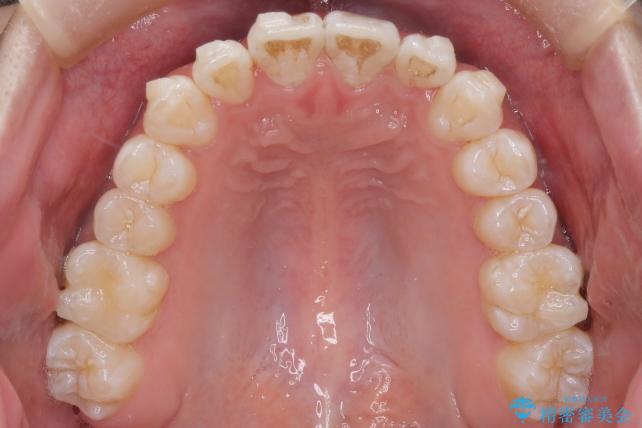

検査したところ叢生量などを考慮し当院の判断として非抜歯での治療が可能と判断しました。

特に下顎前歯の叢生(がたつき)につきましては、きれいに配列させるだけのスペースが現状なかったため、遠心移動とIPR(歯と歯の間を少し削る)を行うことで確保しました。

患者様の意識も高くしっかりと装着していただけたため、計画通りのきれいな歯列弓となりました。仕上がりにとてもご満足いただけました。